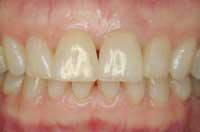

Before and after photos of the same patient.

Functional stability, health, and youthful appearance were achieved with the single implant.

The surgeon who placed the implant is Dr. Leonard Garfinkel of Aventura, Fla.